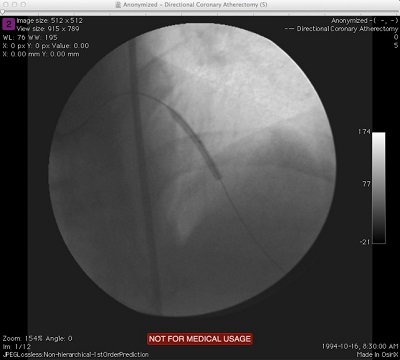

Extracting Image Data to Files (Multi-Frame)

When the convertFileToEightBitImage method is invoked on multi-frame DICOM files, the output file names will be postfixed with the frame number before the format extension. So, for a DICOM file containing two frames of image data for instance, specifying "output.jpg" for the output file name will result in two jpg files "output_001.jpg" and "output_002.jpg" created in the output directory. Code illustration is show below. There are a number of other overloads for the convertFileToEightBitImage method as well as other methods in the ConsumerFormatImageMaker class which provide access to the individual frames of a multi-frame DICOM file if we needed them. I will leave it to you to explore them.

package com.saravanansubramanian.dicom.pixelmedtutorial;

import com.pixelmed.display.ConsumerFormatImageMaker;

public class ExportMultiFrameDicomImageDataToOtherImageFormats {

public static void main(String[] args) {

String dicomFile = "D:\\JavaProjects\\Sample Images\\XA-MONO2-8-12x-catheter";

String outputJpgFile = "D:\\JavaProjects\\Sample Images\\Outputs\\XA-MONO2-8-12x-catheter.jpg";

try {

//Will result in 16 jpeg files created as the input DICOM file has 16 frames

ConsumerFormatImageMaker.convertFileToEightBitImage(dicomFile, outputJpgFile, "jpeg", 0);

} catch (Exception e) {

e.printStackTrace(); //in real life, do something about this exception

}